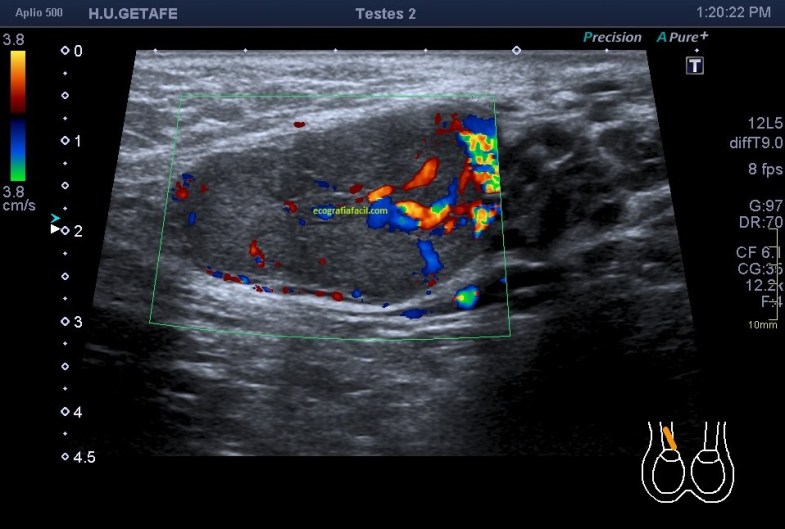

311. Doppler color y Modo Angio, dos secretos que igual no sabías.

Cuando realizamos una exploración ecográfica, el protocolo que sea, no es raro que uno de los comandos que más usemos sea el Doppler, sabemos cómo funciona el Doppler, Alejandro lo ha explicado en este blog y el libro Eco Fácil de Marbán, pero yo quiero contarte dos secretos, que seguro que sabes, pero que quiero contarlo por si hay alguien un poquito más rezagado que aún no se ha enterado.

Quiero que te preguntes si sabrías diferenciar entre una imagen Doppler Color y una imagen en Modo Angio o Doppler Power. Vas a decir que sí, que lo sabes. Y es cierto, en la mayoría de las ocasiones distinguimos estas dos técnicas por el color, una rojo y azul, otra azul o morado, u otras coloraciones según la casa comercial.

Modo Doppler Color

Modo Angio o Doppler Power

Ahora quiero que te preguntes si sabrías decirte que magnitud de la onda ultrasonográfica toma de referencia cada una de los dos comando cuando los activamos para darnos la imagen que estamos buscando…igual aquí tienes alguna dificultad, igual aquí, te he pillado¿Te sonríes?…me encanta…ah que ya lo sabes…bueno, pues lo voy a explicar para quien no lo sepa.

En la onda ultrosonográfica hay dos magnitudes claves, la longitud de onda, que es la distancia entre dos puntos de una misma onda, por ejemplo, entre sus valles o entre sus crestas, que será menor cuanto más alta sea la frecuencia, y la amplitud de la onda que es la máxima distancia que alcanza la onda, o de otro modo, lo enérgica que es esa onda.

Muy bien, en el Doppler Color (CDI) la magnitud de referencia que tomará nuestro equipo para hacer la medición de aquello que estemos interesados en estudiar será la longitud de onda. Sin embargo, en el Doppler Power o Modo Angio (Power) el equipo lee la Amplitud de la onda ultrasonográfica, la imagen de abajo.

Otra de las diferencias entre estos modos de trabajo si lo quieres llamar así es la medición de los hematíes. Me explico, cuando estamos haciendo Doppler lo que medimos es el movimiento hístico. No estamos midiendo las características ecográficas del tejido, es decir, no queremos saber si es anecoico, hipo o hiperecogénico, estamos midiendo su movimiento, el de los vasos, o el de las estructuras que puedan estar vascularizadas.

Por tanto este modo de trabajo valoriza el movimientos de los hematíes, su velocidad, y la densidad de estas células sanguíneas las mide el modo angio, por eso el Doppler color se usa para flujos rápidos (medidad cuantitativa) y el modo angio para flujos lentos (medida cualitativa), por eso el modo angio es mas sensible, así que si eres muy sensible, eres modo angio… ¿lo entiendes?